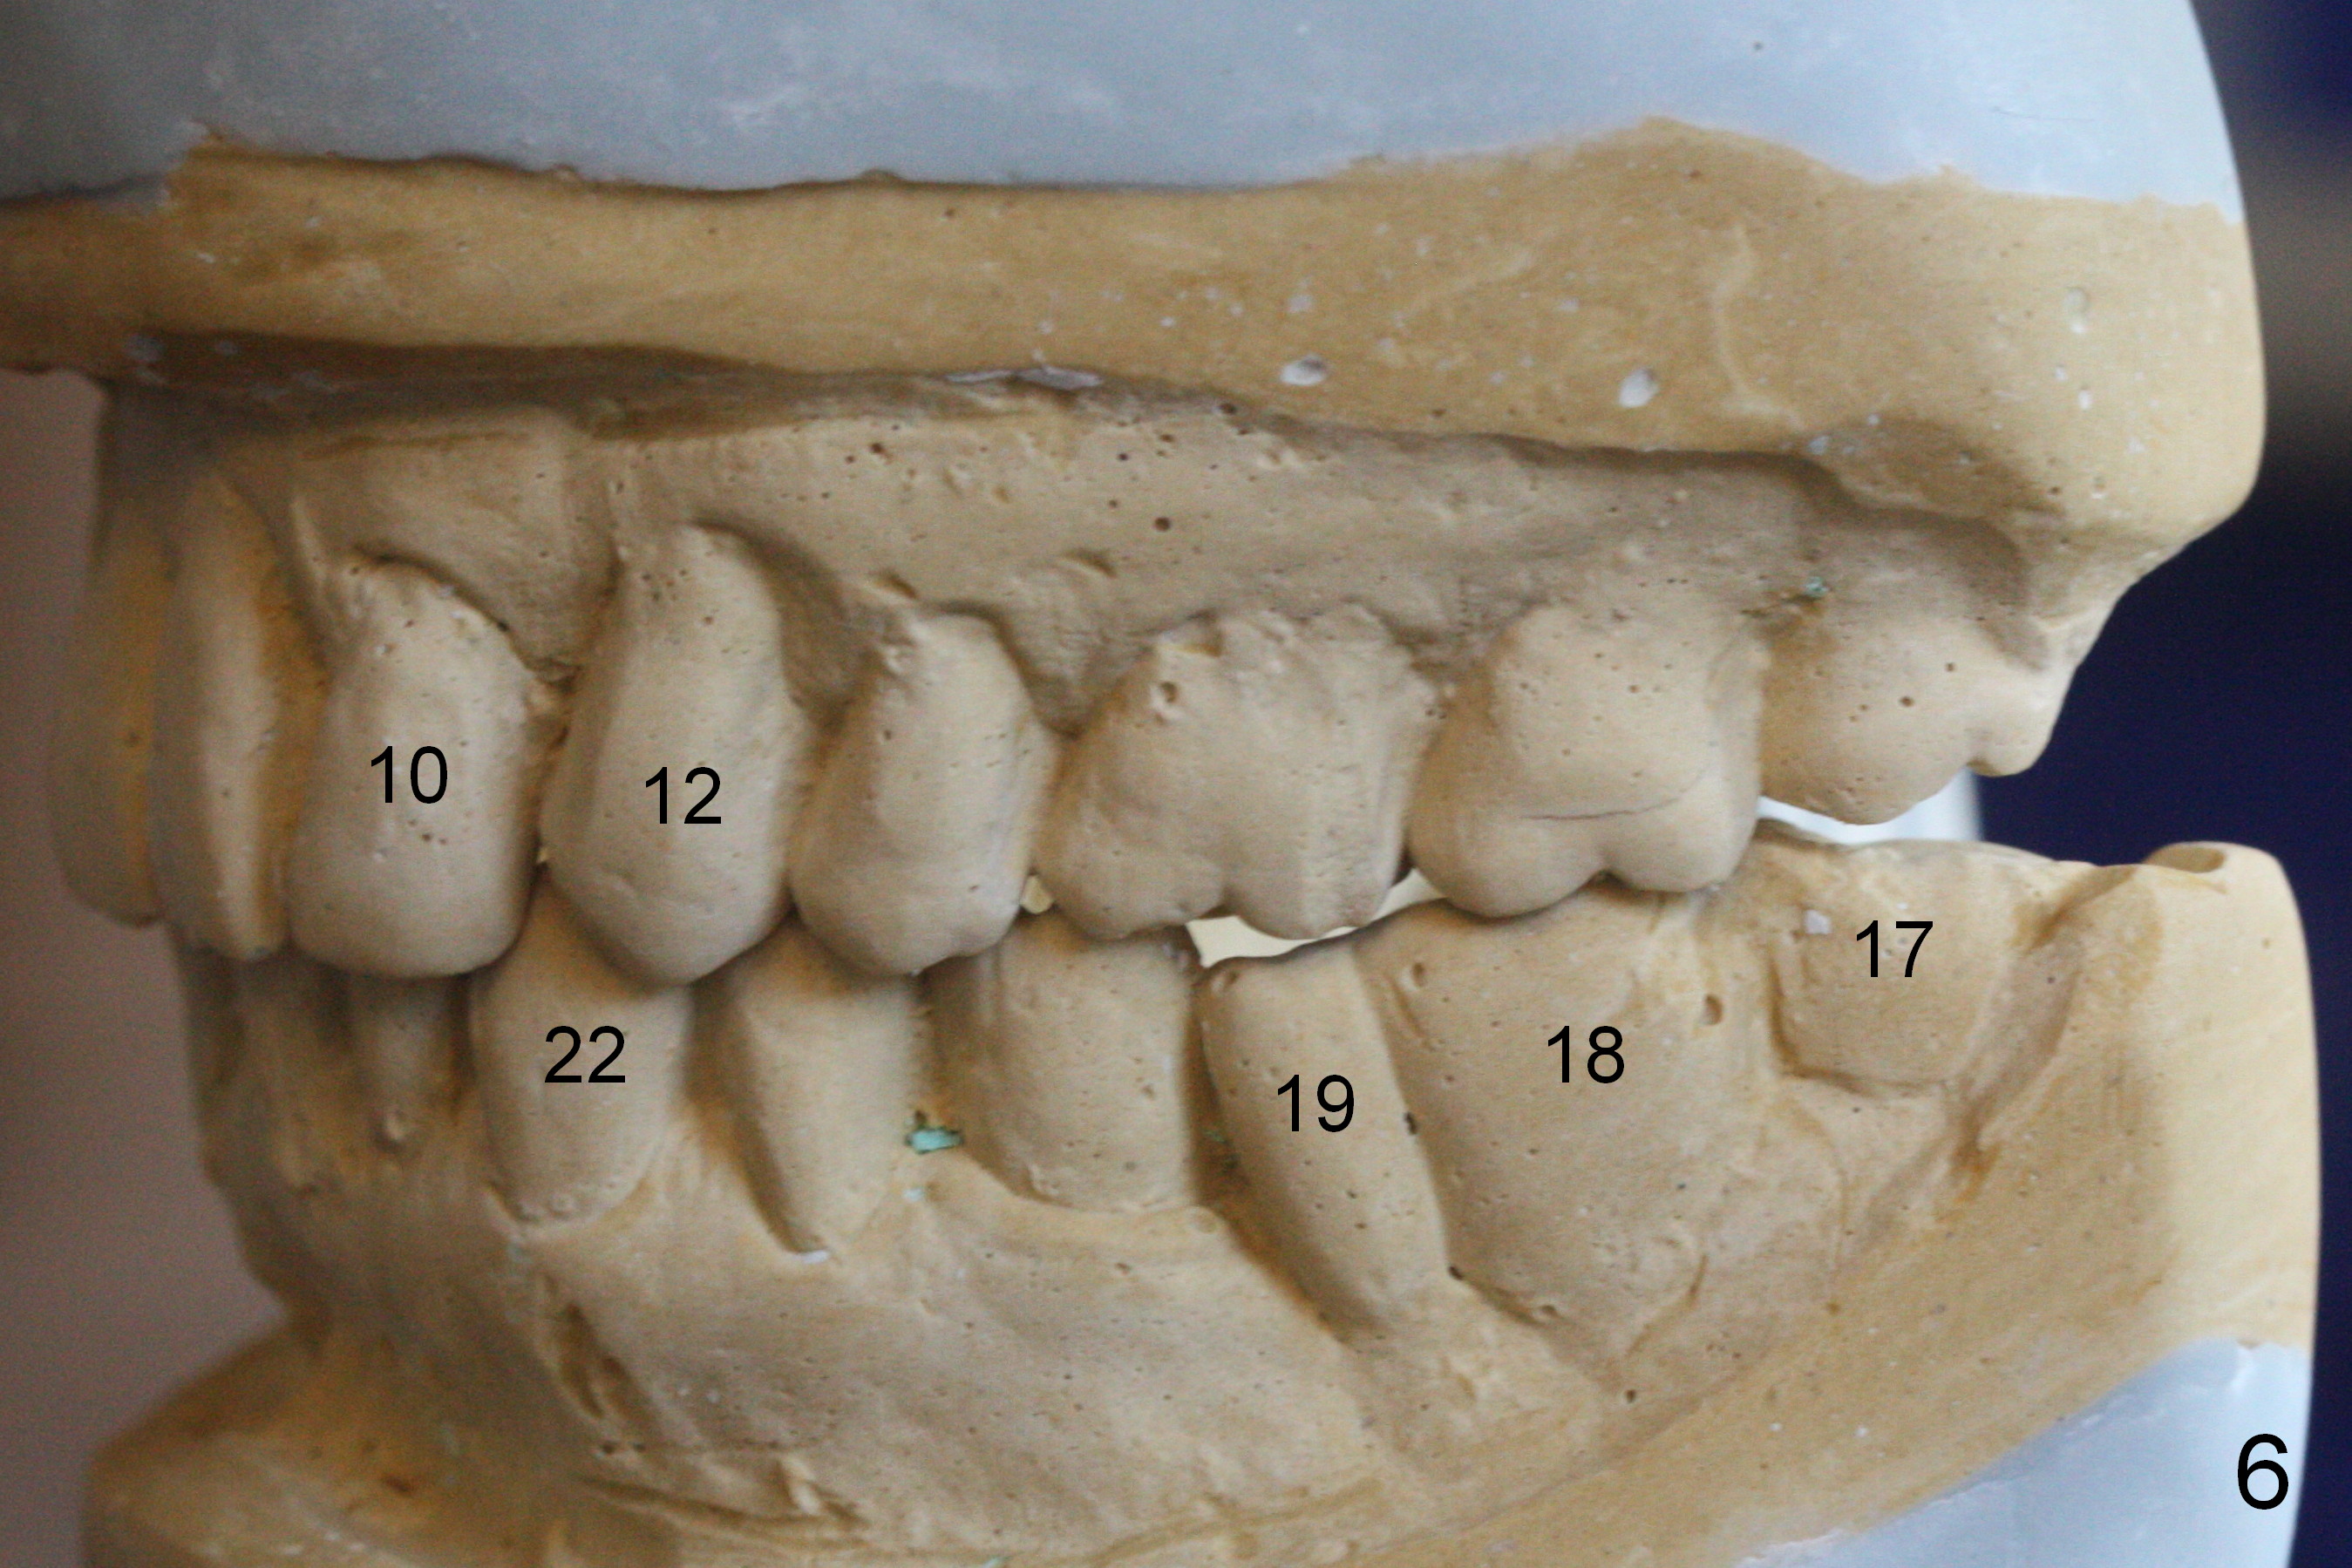

One of the patient's daughter feels that the treatment is too complicated. She would like to have the 2nd molars extracted and implants at the 1st and 2nd molar sites (from Fig.5,6 to 7-9). Since the upper canines are missing (Fig.5,6), the final occlusion will be Class II posteriorly (Fig.8,9).